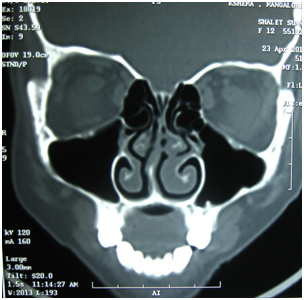

Plain X-rays of the paranasal sinuses are almost obsolete now. CT scan of nose and paranasal sinuses will show the extent of nasal polyp, changes in the sinuses and anatomical variations, which are important considerations if surgical treatment is planned. Coronal CT is the standard view, which provides the required information in most of the cases. Axial view may be required in some cases, especially those with complications. The most important advantage of CT scanning is the precise view of the sinuses and ostiomeatal complex.2 Nasal polyposis will be seen as homogenous soft tissue opacity in the nasal cavity and involved paranasal sinuses (Figure 2). In case of allergic fungal sinusitis, there will be heterogenous soft tissue opacity within the sinuses (Figure 3). Several staging methods have been described for assessment of the degree of inflammatory changes in paranasal sinuses on CT scan, the most commonly used is the Lund-Mackay system. 6

Figure 3 Heterogenous opacity seen in a case of allergic fungal sinusitis with bilateral nasal polyposis.